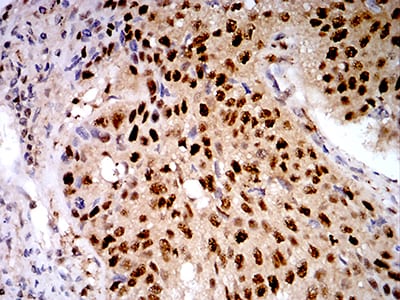

分类: 科研抗体货号: 31022别名: AOF2; CPRF; KDM1; LSD1; BHC110应用: WB,IHC,IF,FCM反应种属: Human